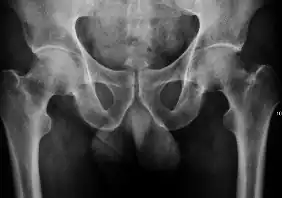

Projectional radiography ("X-ray") is the first imaging technique of choice in hip pain, not only in older people with suspected osteoarthritis but also in young people without any such suspicion. In this case plain radiography allows categorization as normal hip or dysplastic hip, or with impingement signs, pincer, cam, or a combination of both.[1]

X-Ray

Projectional radiography ("X-ray") is currently useful not only in older people in whom osteoarthritis of the hip is suspected but also in younger people without osteoarthritis, who are being evaluated for femoroacetabular impingement (FAI) or hip dysplasia.[1]

Plain radiography allows us to categorize the hip as normal or dysplastic or with impingement signs (pincer, cam, or a combination of both). Besides these, pathologic processes like osteoarthritis, inflammatory diseases, infection, or tumors can also be identified (Figure 1).[1]

Figure 1.